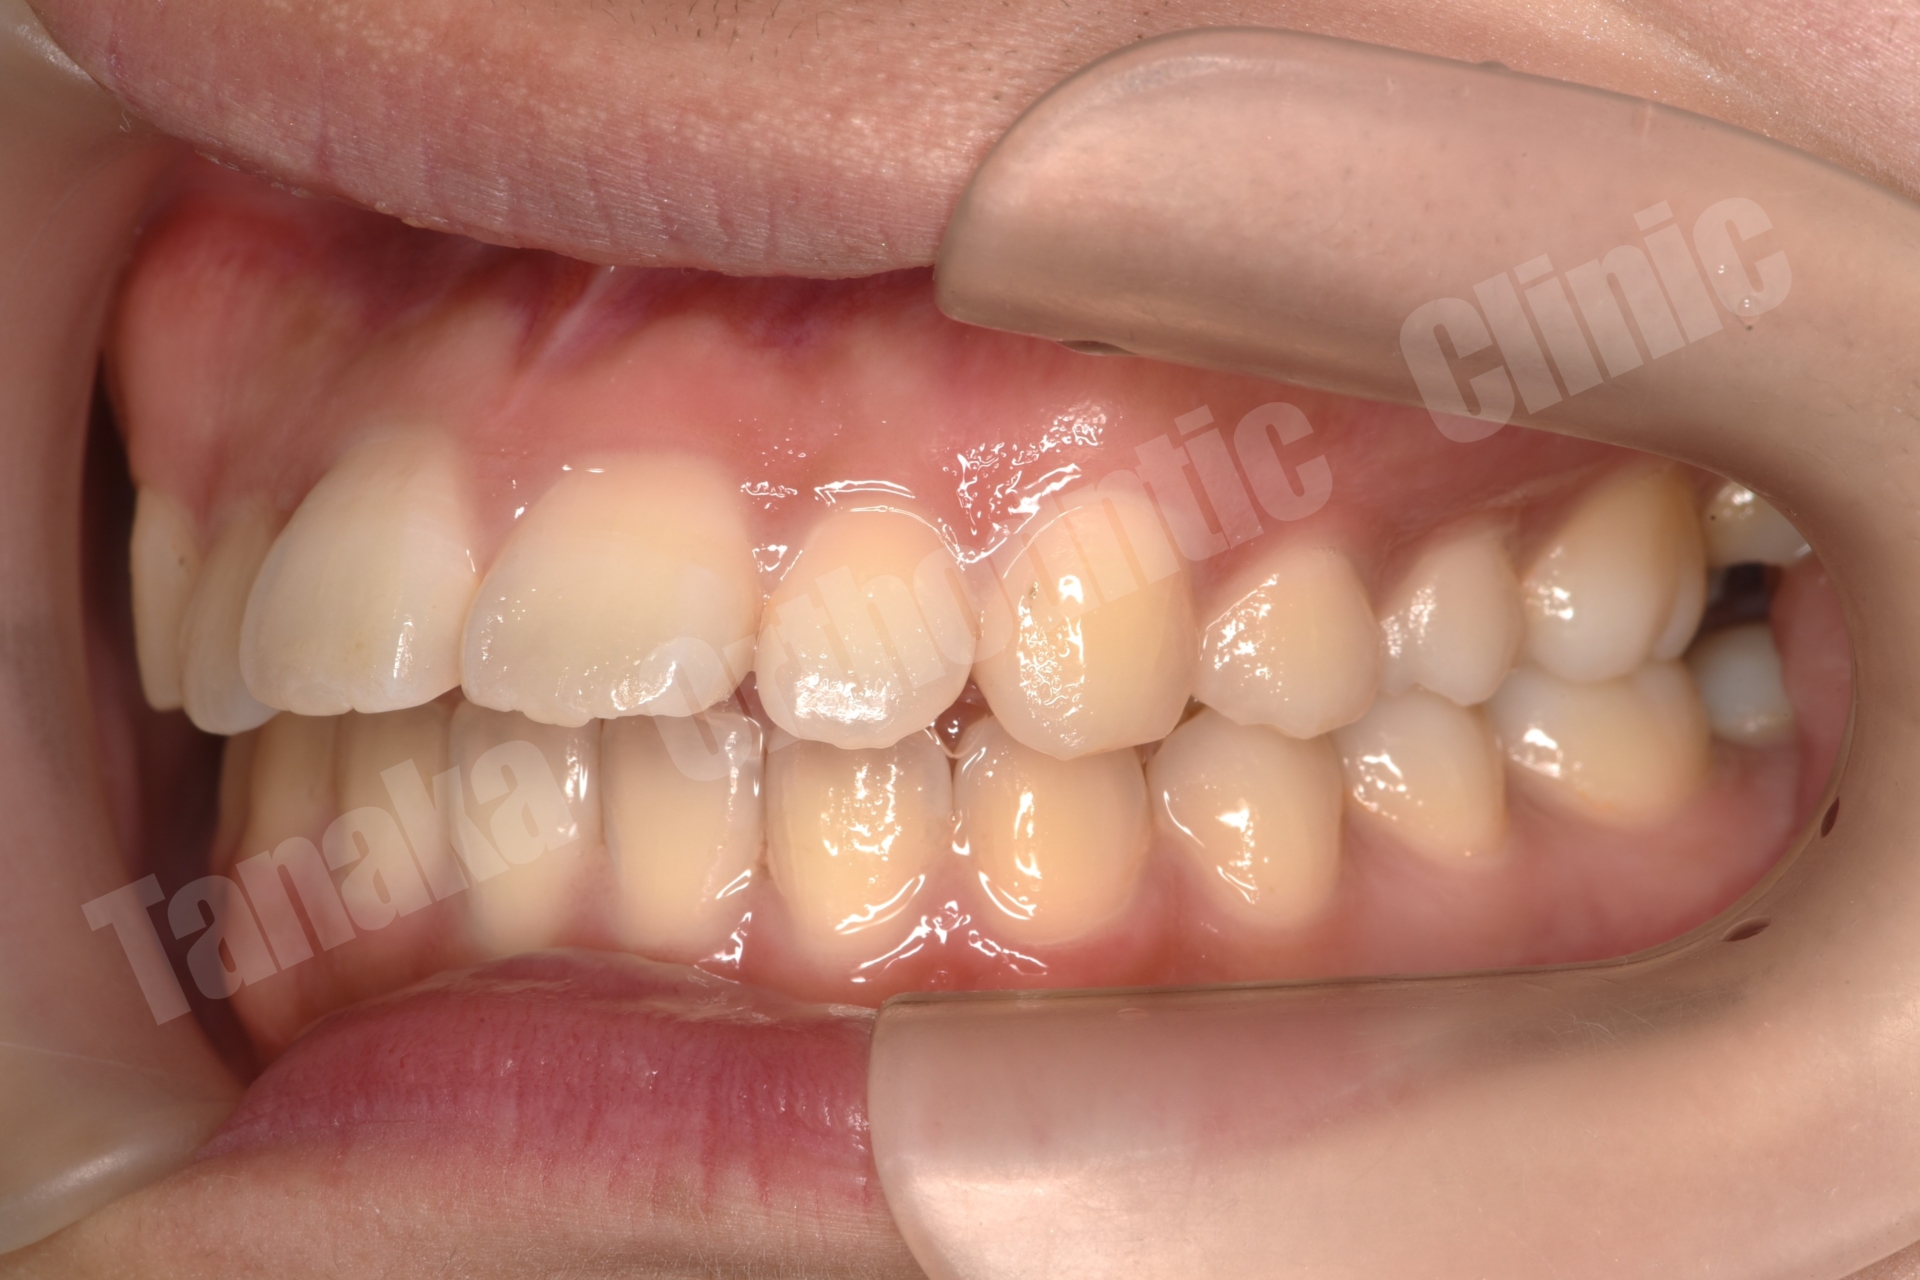

初診時の診査では、上顎前歯が唇側に傾斜しており、前歯の水平被蓋(オーバージェット)が大きい状態でした。そのため口元の突出感が認められ、前歯部は十分に噛んでいない状態でした。また下顎正中は左側へ偏位しており、右下E(乳臼歯)の残存と5番の先天欠如、さらに下顎両側7番の位置異常も確認されました。さらに患者様は10代半ばの頃に一度、非抜歯でマルチブラケット矯正を受けており、その影響もあって上顎中切歯には歯根吸収が生じ、歯根がやや短くなっている所見も認められました。

結果として歯の移動は順調に進み、約1年8か月で治療を終了することができました。気になっていた上顎前歯の突出感と側貌は改善し、前歯の咬み合わせも回復しました。また右下乳臼歯部のスペースを閉鎖することで、将来的にインプラントなどの補綴処置が必要になる可能性も回避することができました。